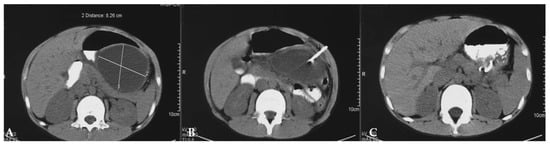

6. Pancreatic Injury

- Ibrahim, A.; Wales, P.W.; Aquino, M.R.; Chavhan, G.B. CT and MRI findings in pancreatic trauma in children and correlation with outcome. Pediatr. Radiol. 2020, 50, 943–952. [Google Scholar] [CrossRef]

- Song, Q.; Tang, J.; Lv, F.Q.; Zhang, Y.; Jiao, Z.Y.; Liu, Q.; Luo, Y.K. Evaluation of blunt pancreatic injury with contrast-enhanced ultrasonography in comparison with contrast-enhanced computed tomography. Exp. Ther. Med. 2013, 5, 1461–1465. [Google Scholar] [CrossRef]

- Miele, V.; Piccolo, C.L.; Sessa, B.; Trinci, M.; Galluzzo, M. Comparison between MRI and CEUS in the follow-up of patients with blunt abdominal trauma managed conservatively. Radiol. Med. 2016, 121, 27–37. [Google Scholar] [CrossRef]